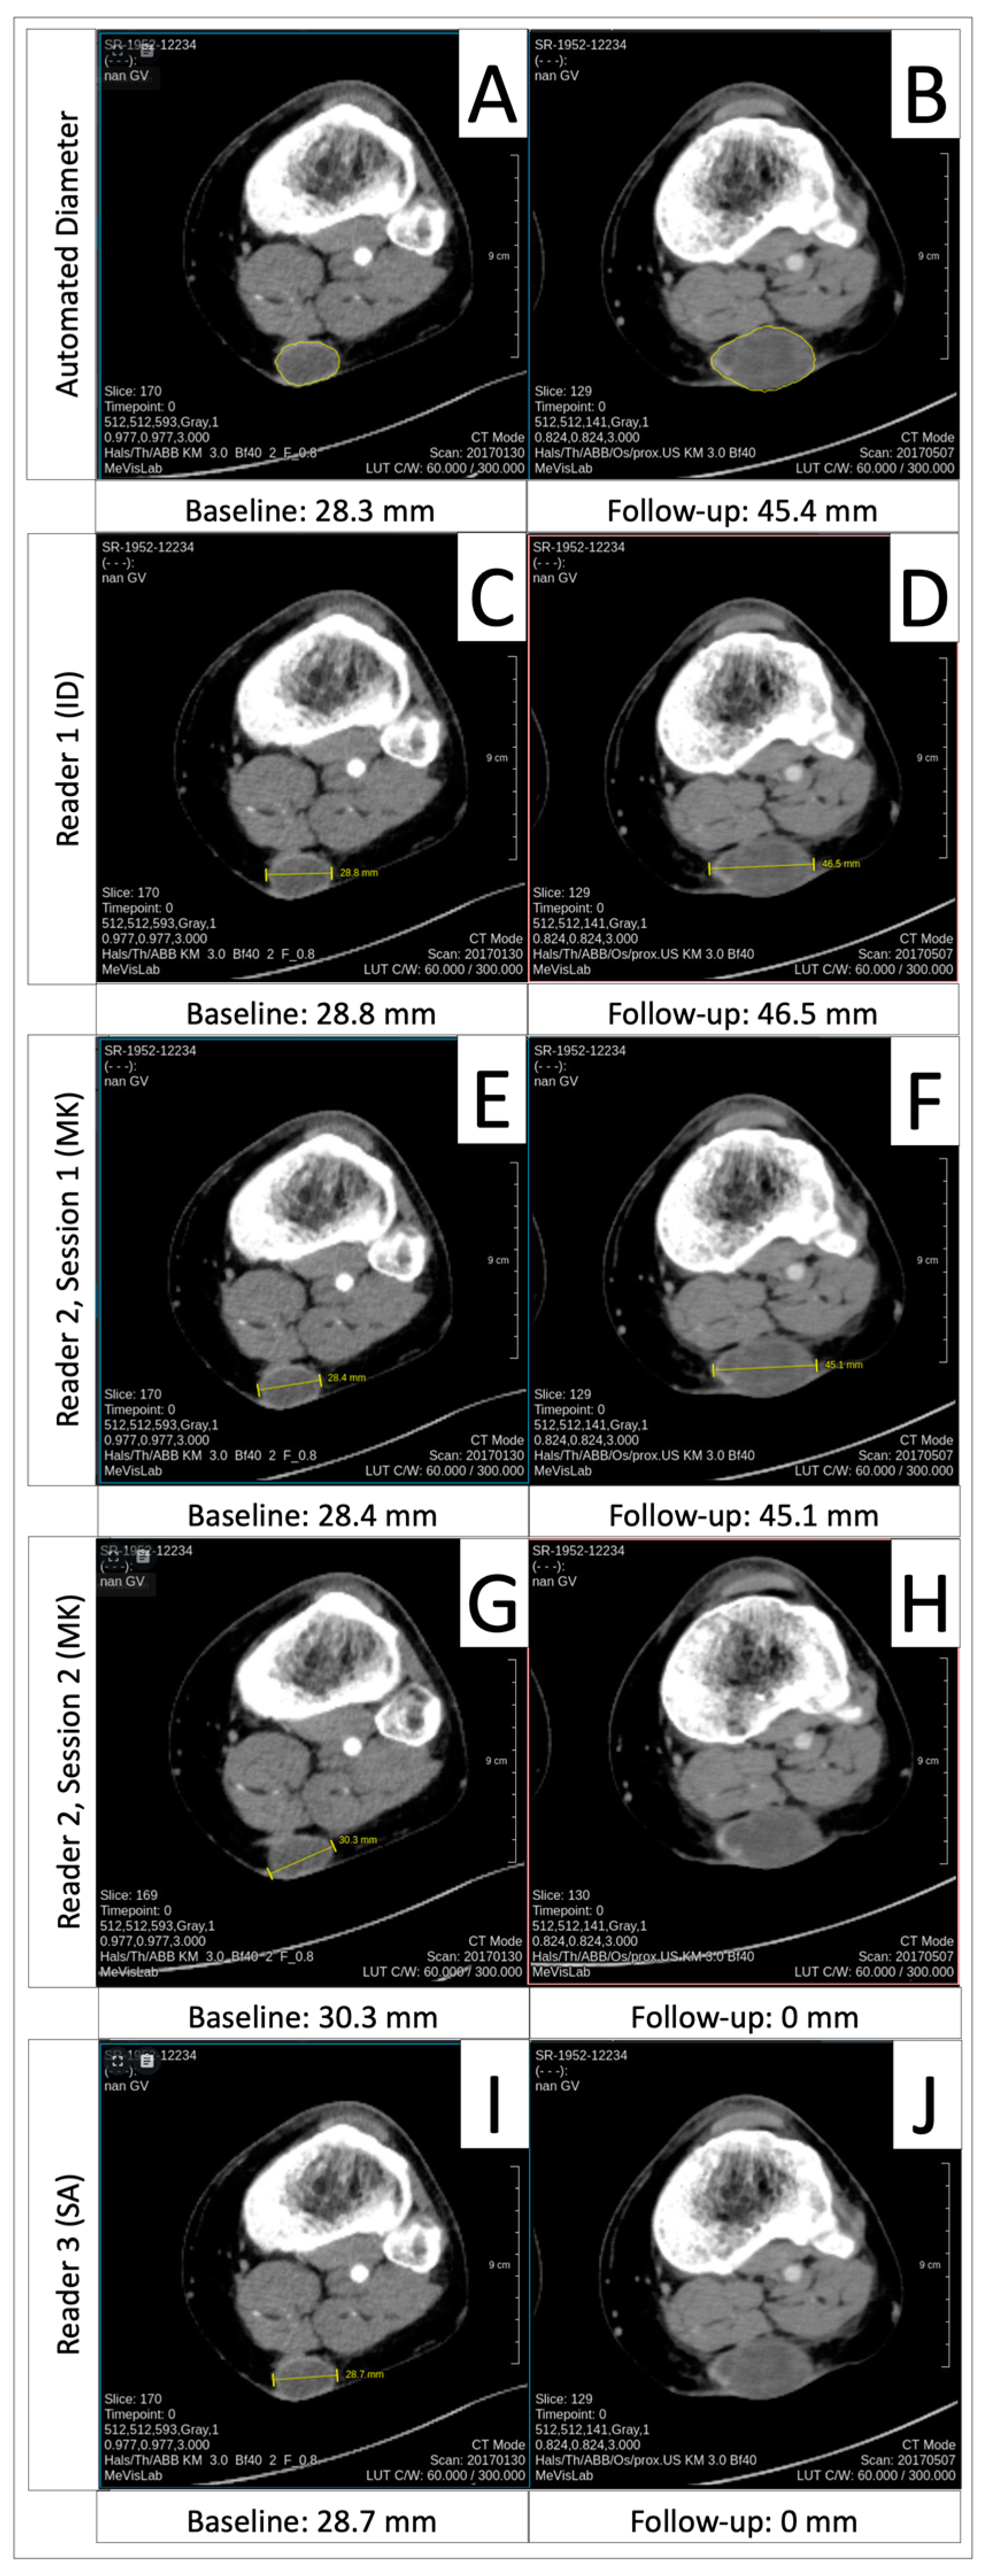

3.6. Progressive Disease Timepoint Response Deviation